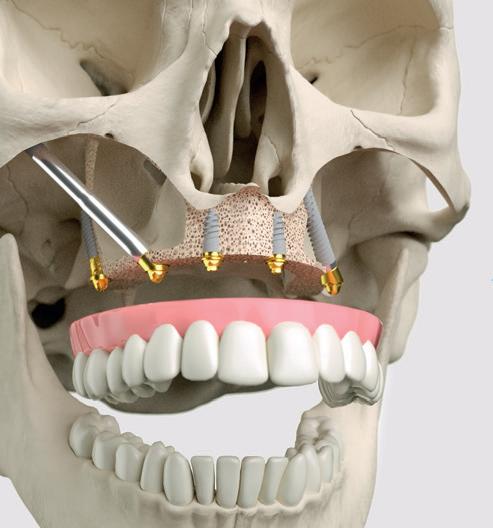

Er zijn wereldwijd enorm veel type implantaten op de markt. Implantaten kunnen van elkaar verschillen in materiaal, oppervlakte, connectie, lengte, breedte, vorm, diepte van en afstand tussen de windingen. De meeste implantaatfabrikanten hebben meerdere type implantaten in hun portfolio, met elk hun specifieke eigenschappen. In deze editie van Vast en Zeker gaan wij in op de vormgeving van het implantaat en de schroefdraad.

Straight of tapered?

De vorm van een implantaat kan recht (vaak aangeduid als ‘straight’) of taps-toelopend (‘tapered’) zijn (afbeelding 2). Een tapered implantaat wordt veelal geadviseerd in situaties waar je meer primaire stabiliteit nodig hebt. Denk hierbij aan implantaatplaatsing in een verse extractie-alveole (zgn. ‘immediate placement’) of in zeer zacht bot (klasse III en IV-bot, veelal in de bovenkaak). Wanneer het bot harder is, dan zal de implantaatplaatsing van een tapered implantaat lastiger zijn. Ook de preparatie voor een tapered implantaat vraagt om meer aandacht. Bij een recht implantaat kan de osteotomie vaak net 1 mm dieper geprepareerd worden dan exact de lengte van het implantaat. Zo is er enige speling bij het plaatsen van het implantaat om deze exact op een juiste diepte in het bot te kunnen plaatsen. Bij een tapered implantaat is het daarentegen niet wenselijk om dieper te prepareren. De preparatie van de osteotomie is namelijk bij de meeste systemen ook tapered van vorm. Daardoor verkrijgt het implantaat pas zijn stabiliteit

als het in zijn laatste fase bij plaatsing contact maakt met het bot en niet over de gehele lengte zoals bij een recht implantaat. Als er 1 mm dieper geprepareerd wordt bij een tapered implantaat, dan zal deze dus ook 1 mm dieper geplaatst moeten worden om voldoende stabiliteit te verkrijgen.

In bepaalde situaties, zoals tussen twee radices met beperkte ruimte of bij een fors teruglopende processus (bovenfront), kan het plaatsen van een tapered implantaat soms een anatomisch voordeel bieden (afbeelding 3). Men moet zich wel realiseren dat het totale oppervlakte van het bot-implantaat-contact minder groot is bij een tapered implantaat in vergelijking met een straight implantaat van dezelfde lengte.

De vorm van de schroefdraad

Schroefdraden kunnen verschillende vormen hebben. Soms verandert de vorm van een schroefdraad

1. Implantaten met verschillende soorten windingen.

2. Recht implantaat (links) en een tapered implantaat (rechts).

3. Een situatie waarbij een tapered implantaat beter uitkomt dan een straight implantaat.

4. Binnen hetzelfde implantaat worden in dit geval verschillende vormen schroefdraad gebruikt: de kleine windingen hebben een V-vorm, dan volgt er een rechthoekige schroefdraad waarna er een zgn. reverse buttress vorm schroefdraad volgt. De diepte van de schroefdraad is apicaal dieper dan coronaal waar de diepte

binnen eenzelfde implantaat van coronaal naar apicaal. Fabrikanten doen dit om zo meer primaire stabiliteit te bereiken voor het implantaat. Zo zal het apicale gedeelte van de schroefdraad vaak een snijdende vorm hebben om zich door het bot te kunnen werken. Meer richting coronaal kunnen de windingen dikker worden om het bot meer te comprimeren om zodoende meer stabiliteit te verkrijgen.

van de schroefdraad steeds meer afneemt.

5. Implantaat met twee schroefdraden (aangegeven met rood en blauw).

6. Bij een snijdend implantaat is de opvangkamer voor het botgruis goed zichtbaar (zie rode cirkel).

De vier belangrijkste vormen schroefdraad zijn (afbeelding 4):

1. V-vorm

2. Rechthoekige vorm

3. Buttress vorm

4. Reverse buttress vorm

De vorm van de schroefdraad beïnvloedt de krachten-

verdeling op het spongieuze bot. In het corticale bot blijkt de vorm van de windingen een minder grote rol te spelen. De rechthoekige vorm schroefdraad blijkt de meest gunstige drukbelasting op het bot te geven. De V-vorm daarentegen de minst gunstige krachten.1

De diepte van de schroefdraden speelt een rol bij de primaire stabiliteit van het implantaat. Hoe dieper de schroefdraad, des te meer deze zich zal vastgrijpen in het bot. Dit kan binnen hetzelfde implantaat gevarieerd worden, zoals te zien is op foto 4.

De steilheid van de schroefdraad bepaalt de snelheid waarmee het implantaat in de osteotomie geplaatst wordt. Als de schroefdraden minder steil zijn, dan zal het implantaat bij één volledige rotatie minder ver in het bot wegzakken dan wanneer de schroefdraad steiler is. De diepte waarmee het implantaat bij één volledige omwenteling wegzakt wordt ook wel de “lead” genoemd (afbeelding 5).2

Een implantaat kan ook twee schroefdraden boven elkaar bevatten. De schroefdraad wordt dan ook steiler. Ofwel, de lead wordt groter. De afstand tussen beide schroefdraden wordt ook wel de “pitch” genoemd. Onderzoek geeft aan dat een enkele schroefdraad meer stabiliteit geeft dan een dubbele schroefdraad. Veelal zijn dit soort onderzoeken computermodellen, die dan ook met voorzichtigheid dienen te worden geïnterpreteerd.3

Het toevoegen van windingen zal met name de indraaisnelheid van het implantaat verhogen.

Implantaten zijn van oudsher recht en stomp. Een hoge primaire stabiliteit bleek niet zozeer noodzakelijk voor een voorspoedige inheling. Stompe implantaten volgen volledig de osteotomie en zijn niet meer van asrichting te wijzigen. Te hoge compressie op het bot, en daarmee botnecrose, zal bij plaatsing van deze stompe implantaten volgens het boorprotocol dan ook niet snel voorkomen. Door het aanbrengen van diepere, scherpere windingen en een ‘opvangkamer’ voor het vrijgekomen bot, zal een implantaat

meer snijdend zijn (afbeelding 6). De opvangkamer is vaak goed te herkennen aan het implantaat als een ruimte in het apicale gedeelte. De opvangkamer zal vollopen met het vrijgekomen bot waardoor het implantaat minder snel vast loopt. Met een snijdend implantaat kan de asrichting indien gewenst nog iets worden gewijzigd en kan een hogere primaire stabiliteit worden bereikt, met meestal directe belasting van het implantaat als doel.

Implantaten kunnen zowel recht als tapered zijn. Tapered implantaten bieden soms anatomische voordelen, maar worden meestal gebruikt om een hogere primaire stabiliteit te verkrijgen. Een implantaat kan variëren in type, diepte en steilheid van de windingen. Zowel de vorm van een implantaat als de windingen spelen een rol in het gebruiksgemak en stabiliteit van het implantaat. Een implantoloog dient per situatie in te kunnen schatten welk type implantaat de meest optimale eigenschappen heeft.